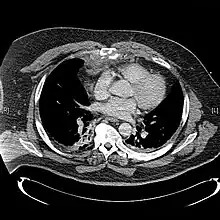

| A displaced sternal fracture as seen on plain X-ray | |

X-rays of the chest are taken in people with chest trauma and symptoms of sternal fractures, and these may be followed by CT scanning.[13] Since X-rays taken from the front may miss the injury, they are taken from the side as well.[14]